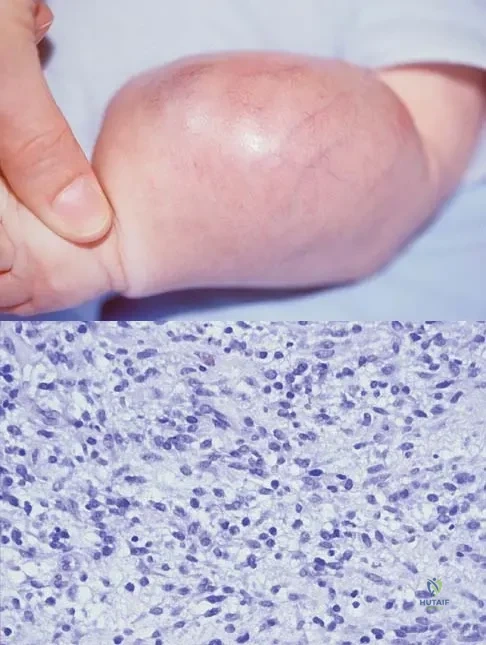

Question 82High Yield

An infant is born with a mass that involves both the volar and dorsal compartments of the left arm. A clinical photograph and biopsy specimen are shown in Figures 41a and 41b. What is the best initial course of action?

Explanation